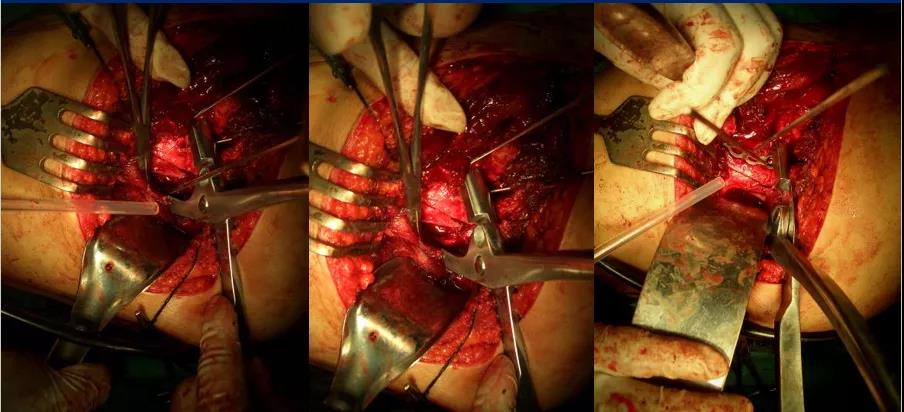

2、一般先选择骨折移位大、粉碎较严重的后柱后壁骨折一侧 3、常先采取Kocher-Langenbeck后入路切口,改半俯卧位;切口:髂后上棘外下4cm处→经大转子顶点→ 垂直向下约5cm, 显露后柱后壁骨折

4、 以骨撬分别放在髂棘、坐骨大切迹、坐骨小切迹,显露后柱后壁骨折

5、根据CT情况探查关节腔,清除关节内的碎骨片; 6、a:解剖复位髋臼后柱及后壁;b:以重建钢板固定 c:纱布填塞切口 d:行C型臂透视了解前壁或前柱骨折复位情况;

7、后柱后壁解剖复位后,由于关节囊完整,前柱一般都能自然复位,对于后柱复位后,前柱骨折移位仍明显且复位该部位能明显修复整个髋臼的解剖序列和减少术后并发症的枢纽部位作为前入路的切开部位。前入路微创切口沿髂耻嵴插板,行前柱重建钢板内固定;

8、若采取前路髂腹股沟入路,改半仰卧位;切口:髂嵴和耻骨联合上;2 cm 两部位取切口;腹股沟区域不予切开显露

9、根据需要分别暴露前壁及前柱骨折部位:术中注意避免损伤髂腰肌及股神经束、髂外血管、精索或圆韧带死亡冠动脉

10、沿髂耻嵴插板,在耻骨上支用2枚螺钉固定,维持前柱,前壁解剖序列连续性,再髂骨上固定另一枚螺钉,起到断端加压作用。